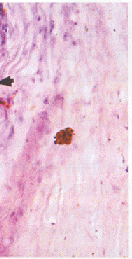

2.2.1 早期 ①小梁:与虹膜根部粘连部分的小梁纤维化,小梁网眼变窄或消失。内皮细胞数减少,部分内皮细胞胞浆中含有色素颗粒。②Schlemm管:基本正常 。③虹膜:仅表现为与小梁粘连处的虹膜变性萎缩,色素颗粒弥散,见图1。

图1 与周边虹膜粘连处的小梁纤维化,小梁网眼变窄,少量色素沉积(箭头);Schlemm管基本正常(箭号)(HE×200)

Fig1 There is trabecular fibrosis in the adhesion area with peripheral iris,some pigment deposition in the trabecular meshwork and the space in trabecular meshwork was narrow(Arrowhead).Schlemm tube is normal(Arrow)(HE×200)